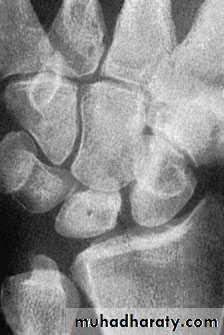

KIENBOCK’S DISEASE

a form of ischaemic necrosis, probably due to chronic stress or injury

Pathology:the pathological changes proceed in four stages

Imaging:

Radioscintigraphy may reveal

increased activity

X-rays

MRI